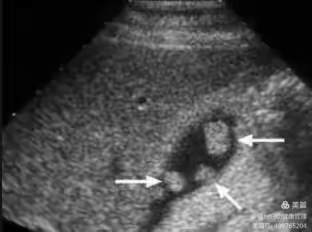

超声检查是胆囊疾病的首选检查手段。

胆囊息肉在常规超声上多表现为胆囊壁上的高回声,后方无声影,不随体位改变而移动